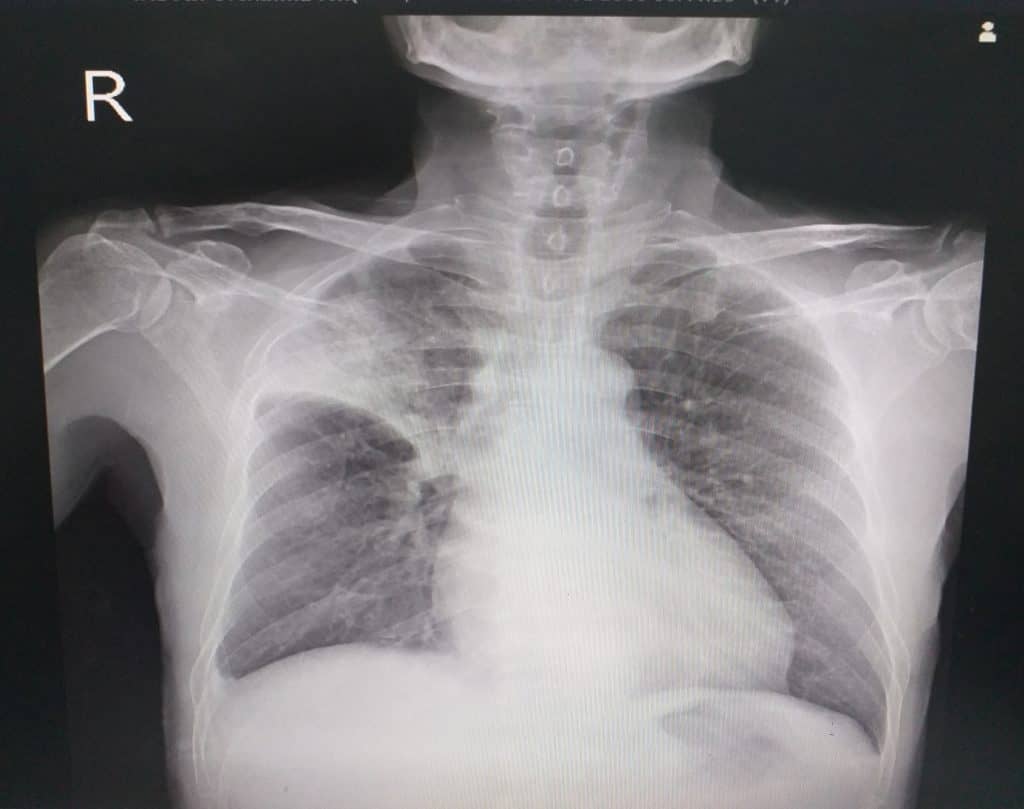

Za dijagnosticiranje atelektaze i utvrđivanje uzroka provode se određeni testovi, uključujući RTG prsnog koša. Na taj način mogu se utvrditi čimbenici koji vrše pritisak na pluća. Ostali testovi koji se koriste za ispitivanje dišnih putova uključuju CT skeniranje, ultrazvuk i oksimetriju. Liječenje ovisi o uzroku ovog problema. U odraslih, atelektaza u malom području pluća obično nije opasna jer pluća mogu nadoknaditi kolabirano područje, donoseći dovoljno kisika za funkcioniranje tijela. Ali ako je zahvaćeno veće područje pluća, to može biti kobno, posebno kod manje djece ili ljudi koji imaju neku drugu plućnu bolest. Kada je atelektaza povezana s ozbiljnim zdravstvenim stanjem, kao što je tumor, tada liječenje uključuje operaciju na zahvaćenom području ili kemoterapiju. U slučaju bakterijske infekcije indicirano je liječenje antibioticima i lijekovima koji olakšavaju iskašljavanje sekreta. Kako bi se smanjio rizik od atelektaze, treba se pridržavati nekih od sljedećih preporuka: primjena vježbi dubokog disanja, jer se na taj način pluća pune zrakom, više pažnje posvetiti infekcijama i bolestima dišnog sustava koje mogu pretvoriti u ozbiljne zdravstvene probleme.